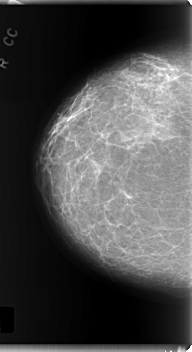

C_0220_1.LEFT_CC

LEFT_CC LINES 5984 PIXELS_PER_LINE 3296 BITS_PER_PIXEL 12 RESOLUTION 50 OVERLAY